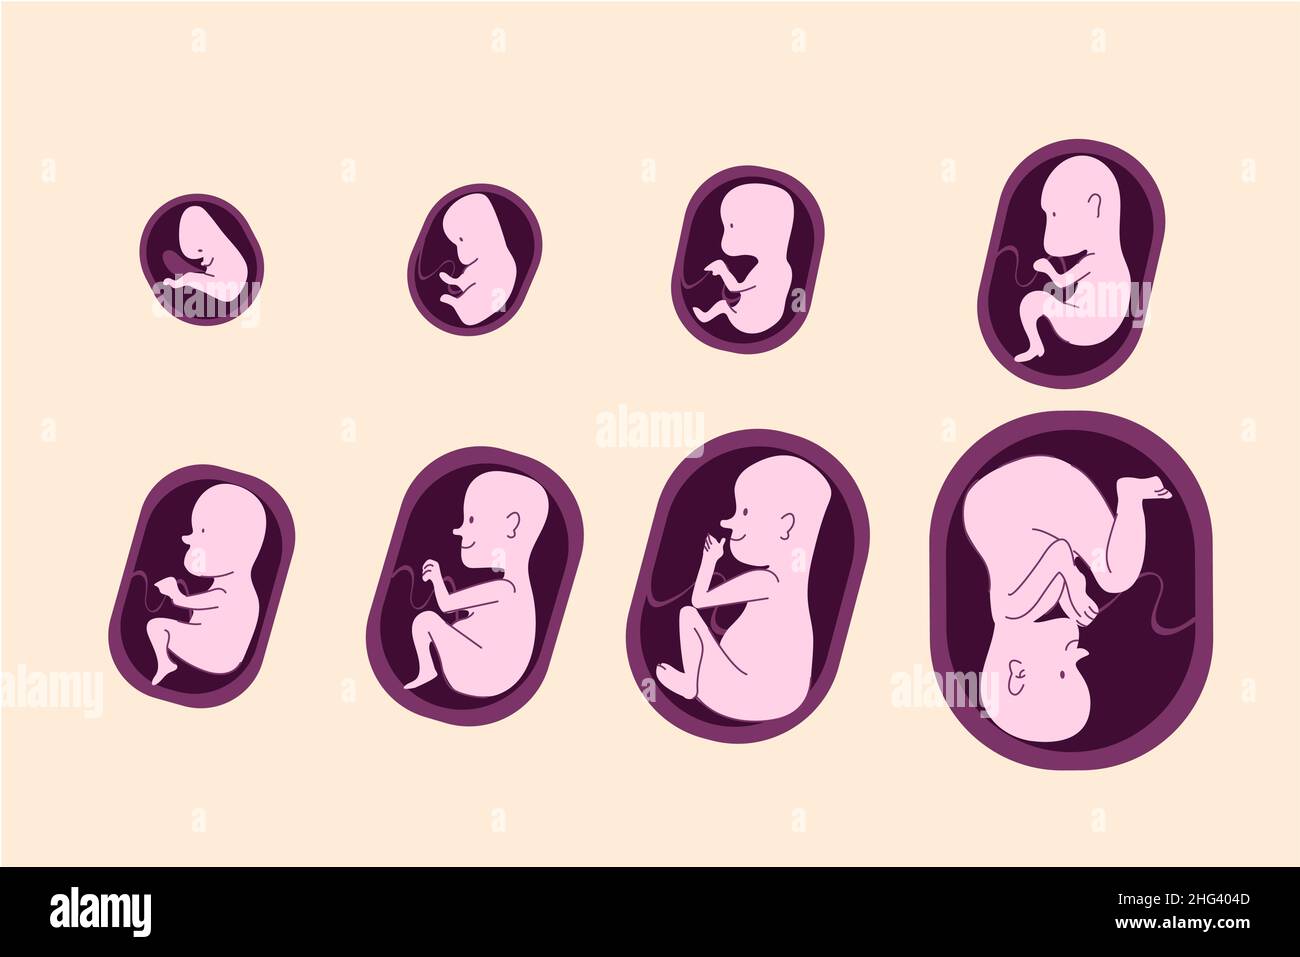

In addition to the information above, here is a curated collection of images related to Fetal Movements Hi Res Stock Photography And Images Alamy.

- 401 Fetal Movement Images, Stock Photos & Vectors | Shutterstock

- Fetal Position Background Illustrations, Royalty-Free Vector Graphics ...